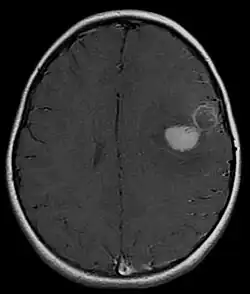

Tumeur neuroectodermique primitive centrale, supratentorielle, chez un patient de cinq ans.

Une tumeur neuroectodermique primitive (PNET) du système nerveux central fait habituellement référence à une tumeur neuroectodermique primitive supratentorielle :